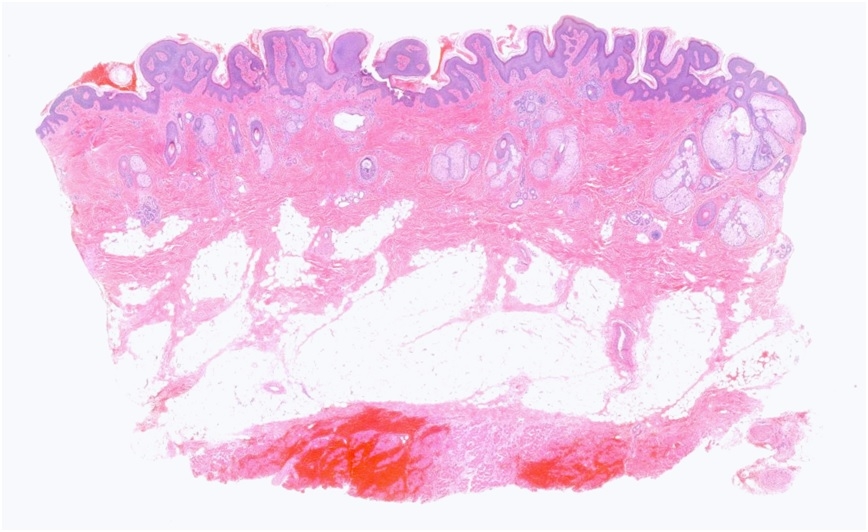

13 M, Left forehead Excision ?Epidermal naevus